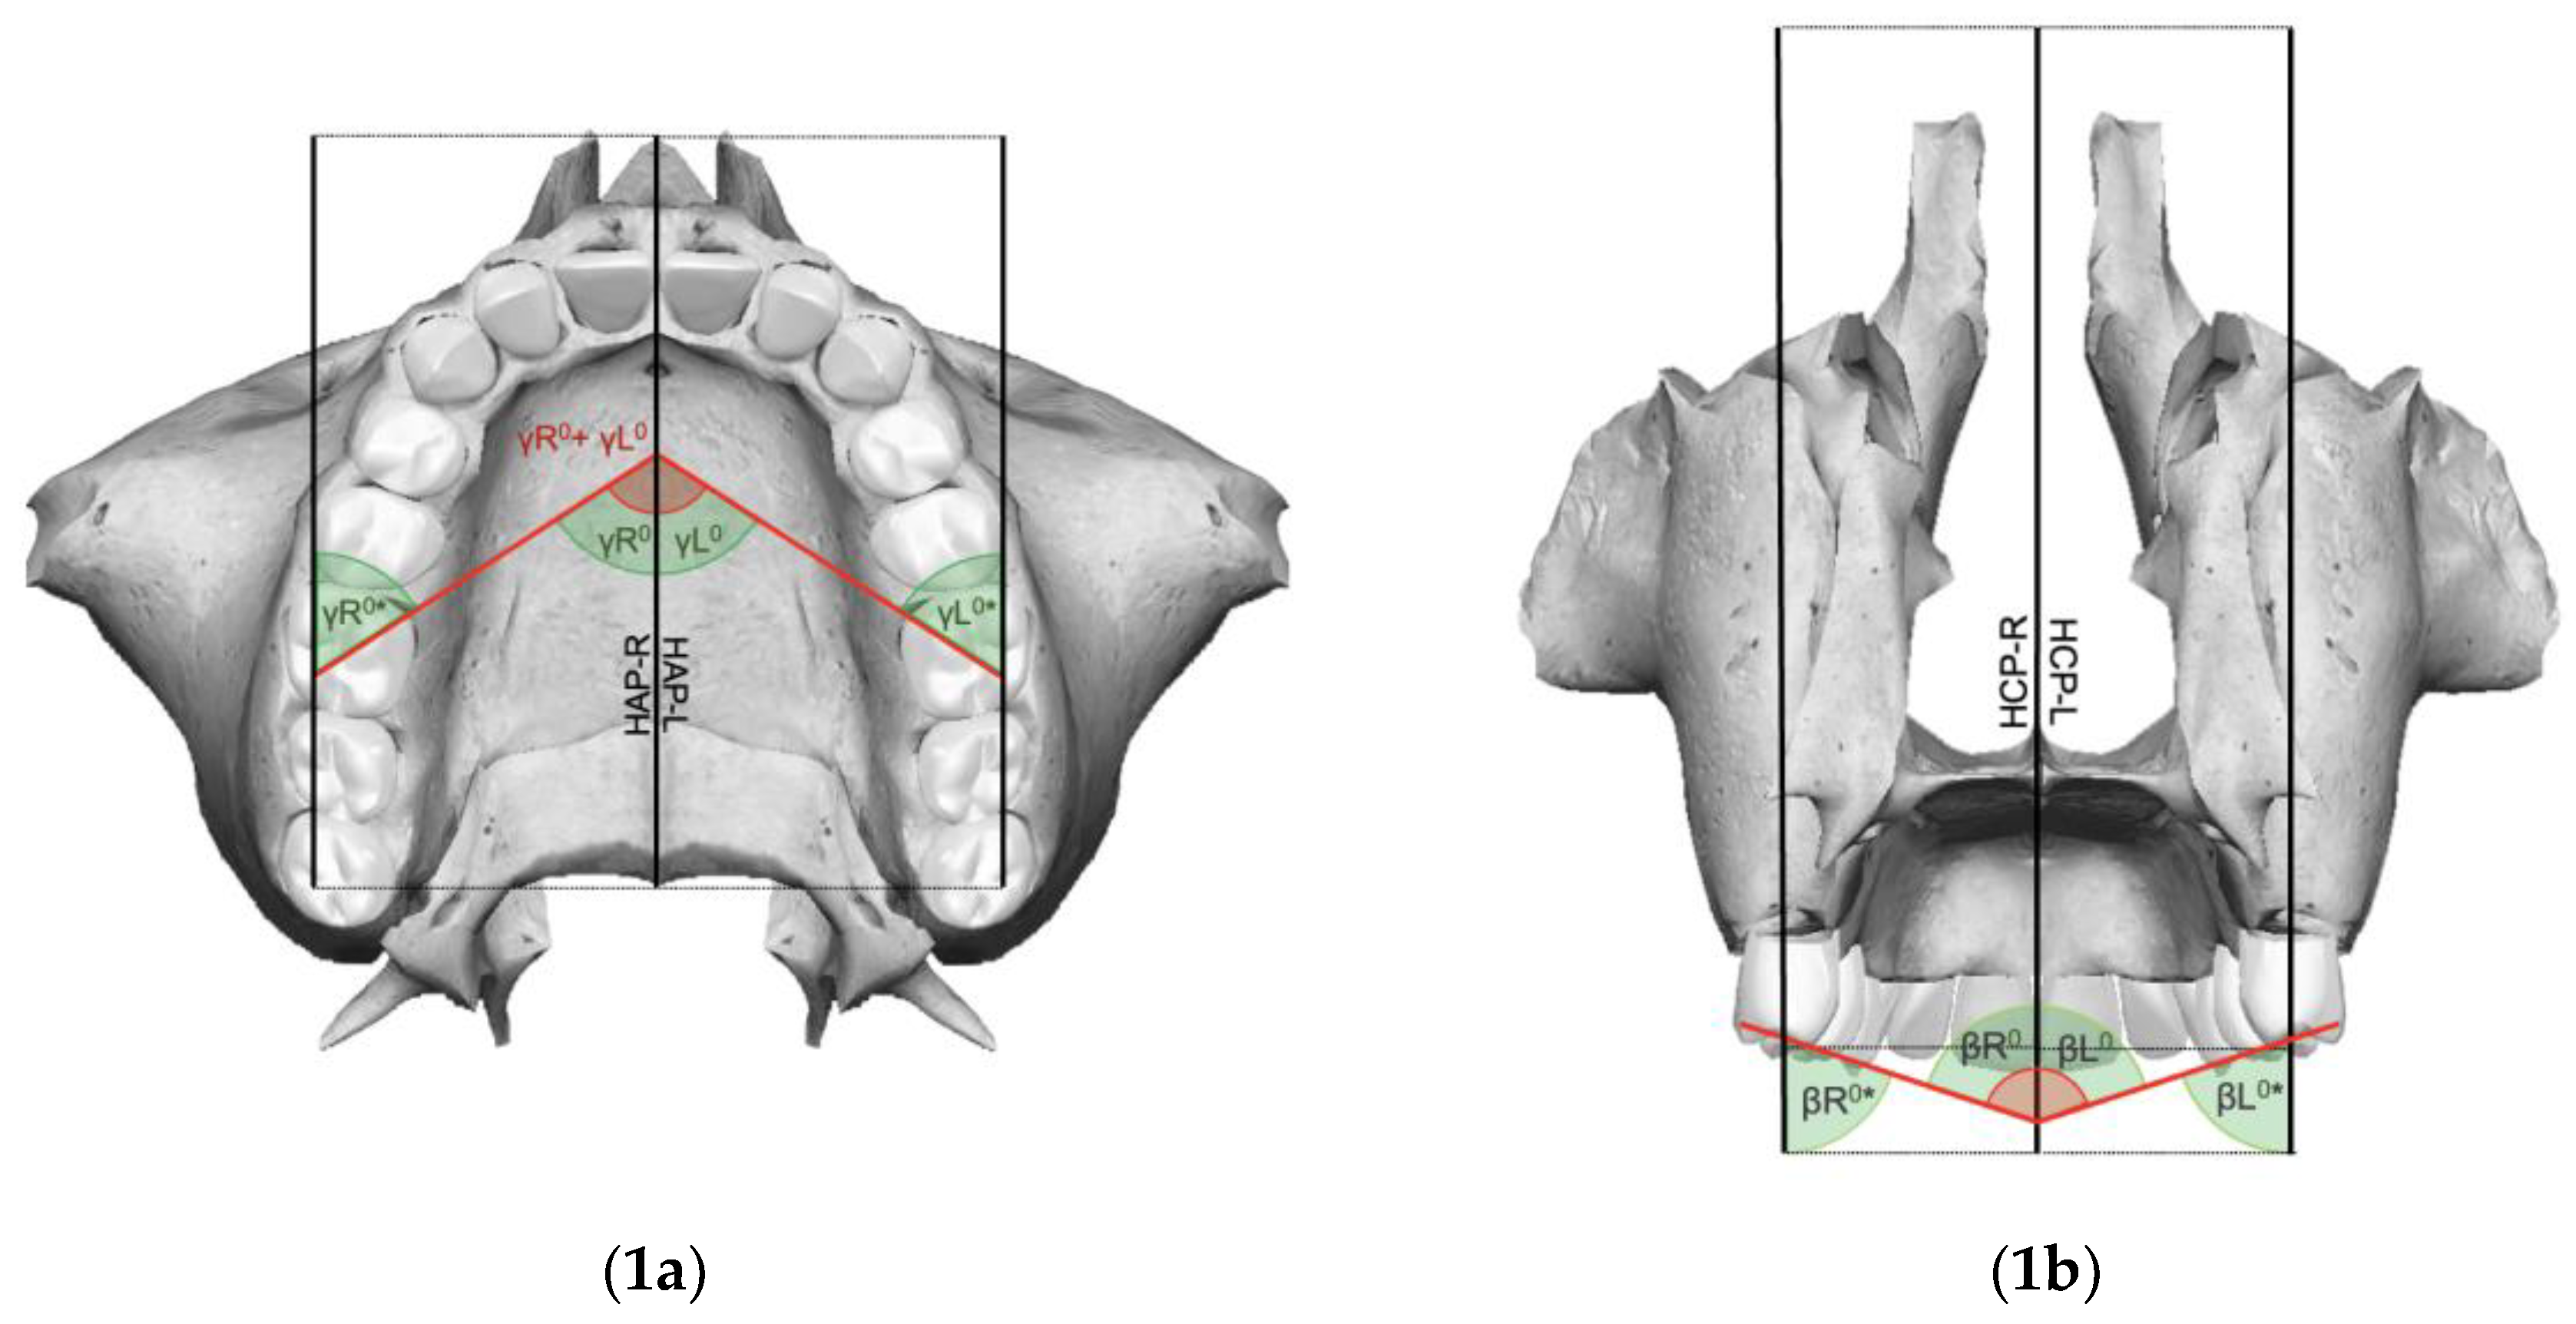

| Hemi Sagittal Plane (HSP) | Plane passing through the Ans (right and left), Pns, and N |

| Hemi Coronal Plane (HCP) | Plane perpendicular to the HSP (right and left) and HAP, passing through the Pns |

| Hemi Axial Plane (HAP) | Plane perpendicular to the HSP (right and left) and HCP, passing through the Pns |

| Intermolar angle (β) | Angle between the MVC and the MPC of the maxillary first molar line of the right and left sides |

| Right molar angle (βR) | Angle generated by the intersection of the maxillary midline with the line joining the MVC and the MPC of the maxillary right first molar |

| Left molar angle (βL) | Angle generated by the intersection of the maxillary midline with the line joining the MVC and the MPC of the maxillary left first molar |

| Molar angle of rotation (γ) | Angle formed by the intersection of the lines passing over the tips of the MPC and the DBC of the right and left maxillary upper first molars |

| Right molar angle of rotation (γR) | Angle formed by the intersection of the line passing over the MPC and the DBC tips of the right maxillary upper first molar and the Ans-Pns segment |

| Left molar angle of rotation (γL) | Angle formed by the intersection of the line passing over the MPC and the DBC tips of the left maxillary upper first molar and the Ans-Pns segment |